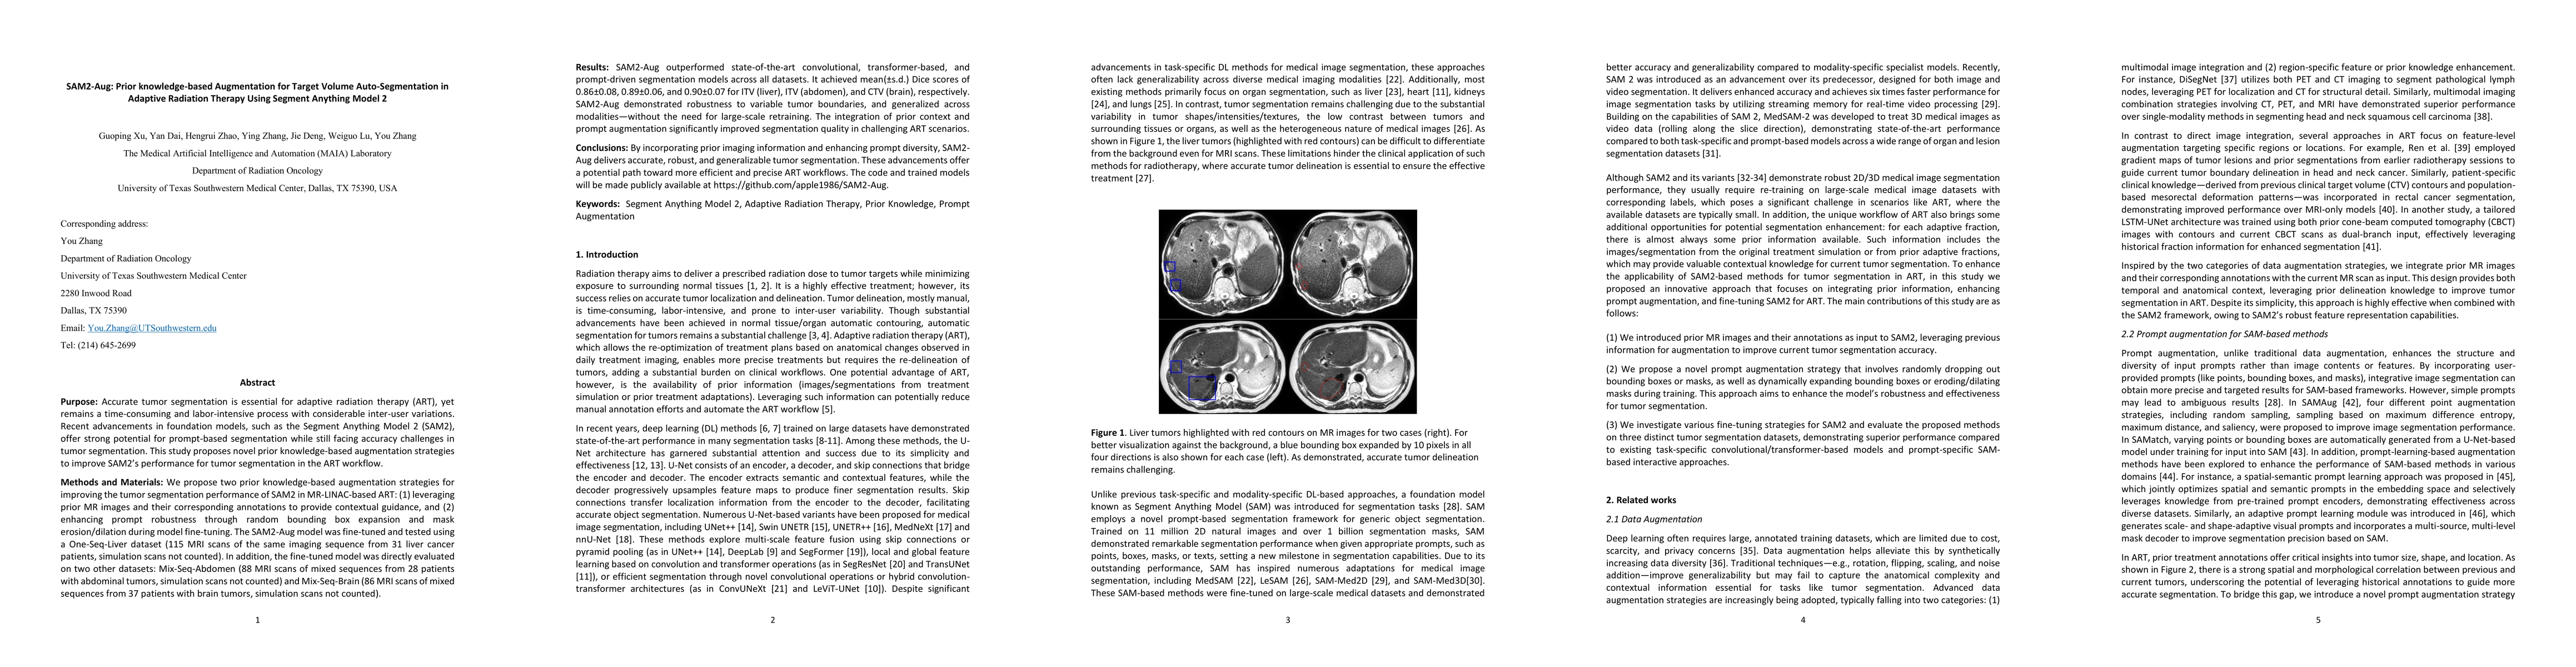

Thumbnail for SAM2-Aug: Prior knowledge-based Augmentation for Target Volume

Auto-Segmentation in Adaptive Radiation Therapy Using Segment Anything Model

2

SAM2-Aug: Prior knowledge-based Augmentation for Target Volume Auto-Segmentation in Adaptive Radiation Therapy Using Segment Anything Model 2

Purpose: Accurate tumor segmentation is vital for adaptive radiation therapy (ART) but remains time-consuming and user-dependent. Segment Anything Model 2 (SAM2) shows promise for prompt-based segment...